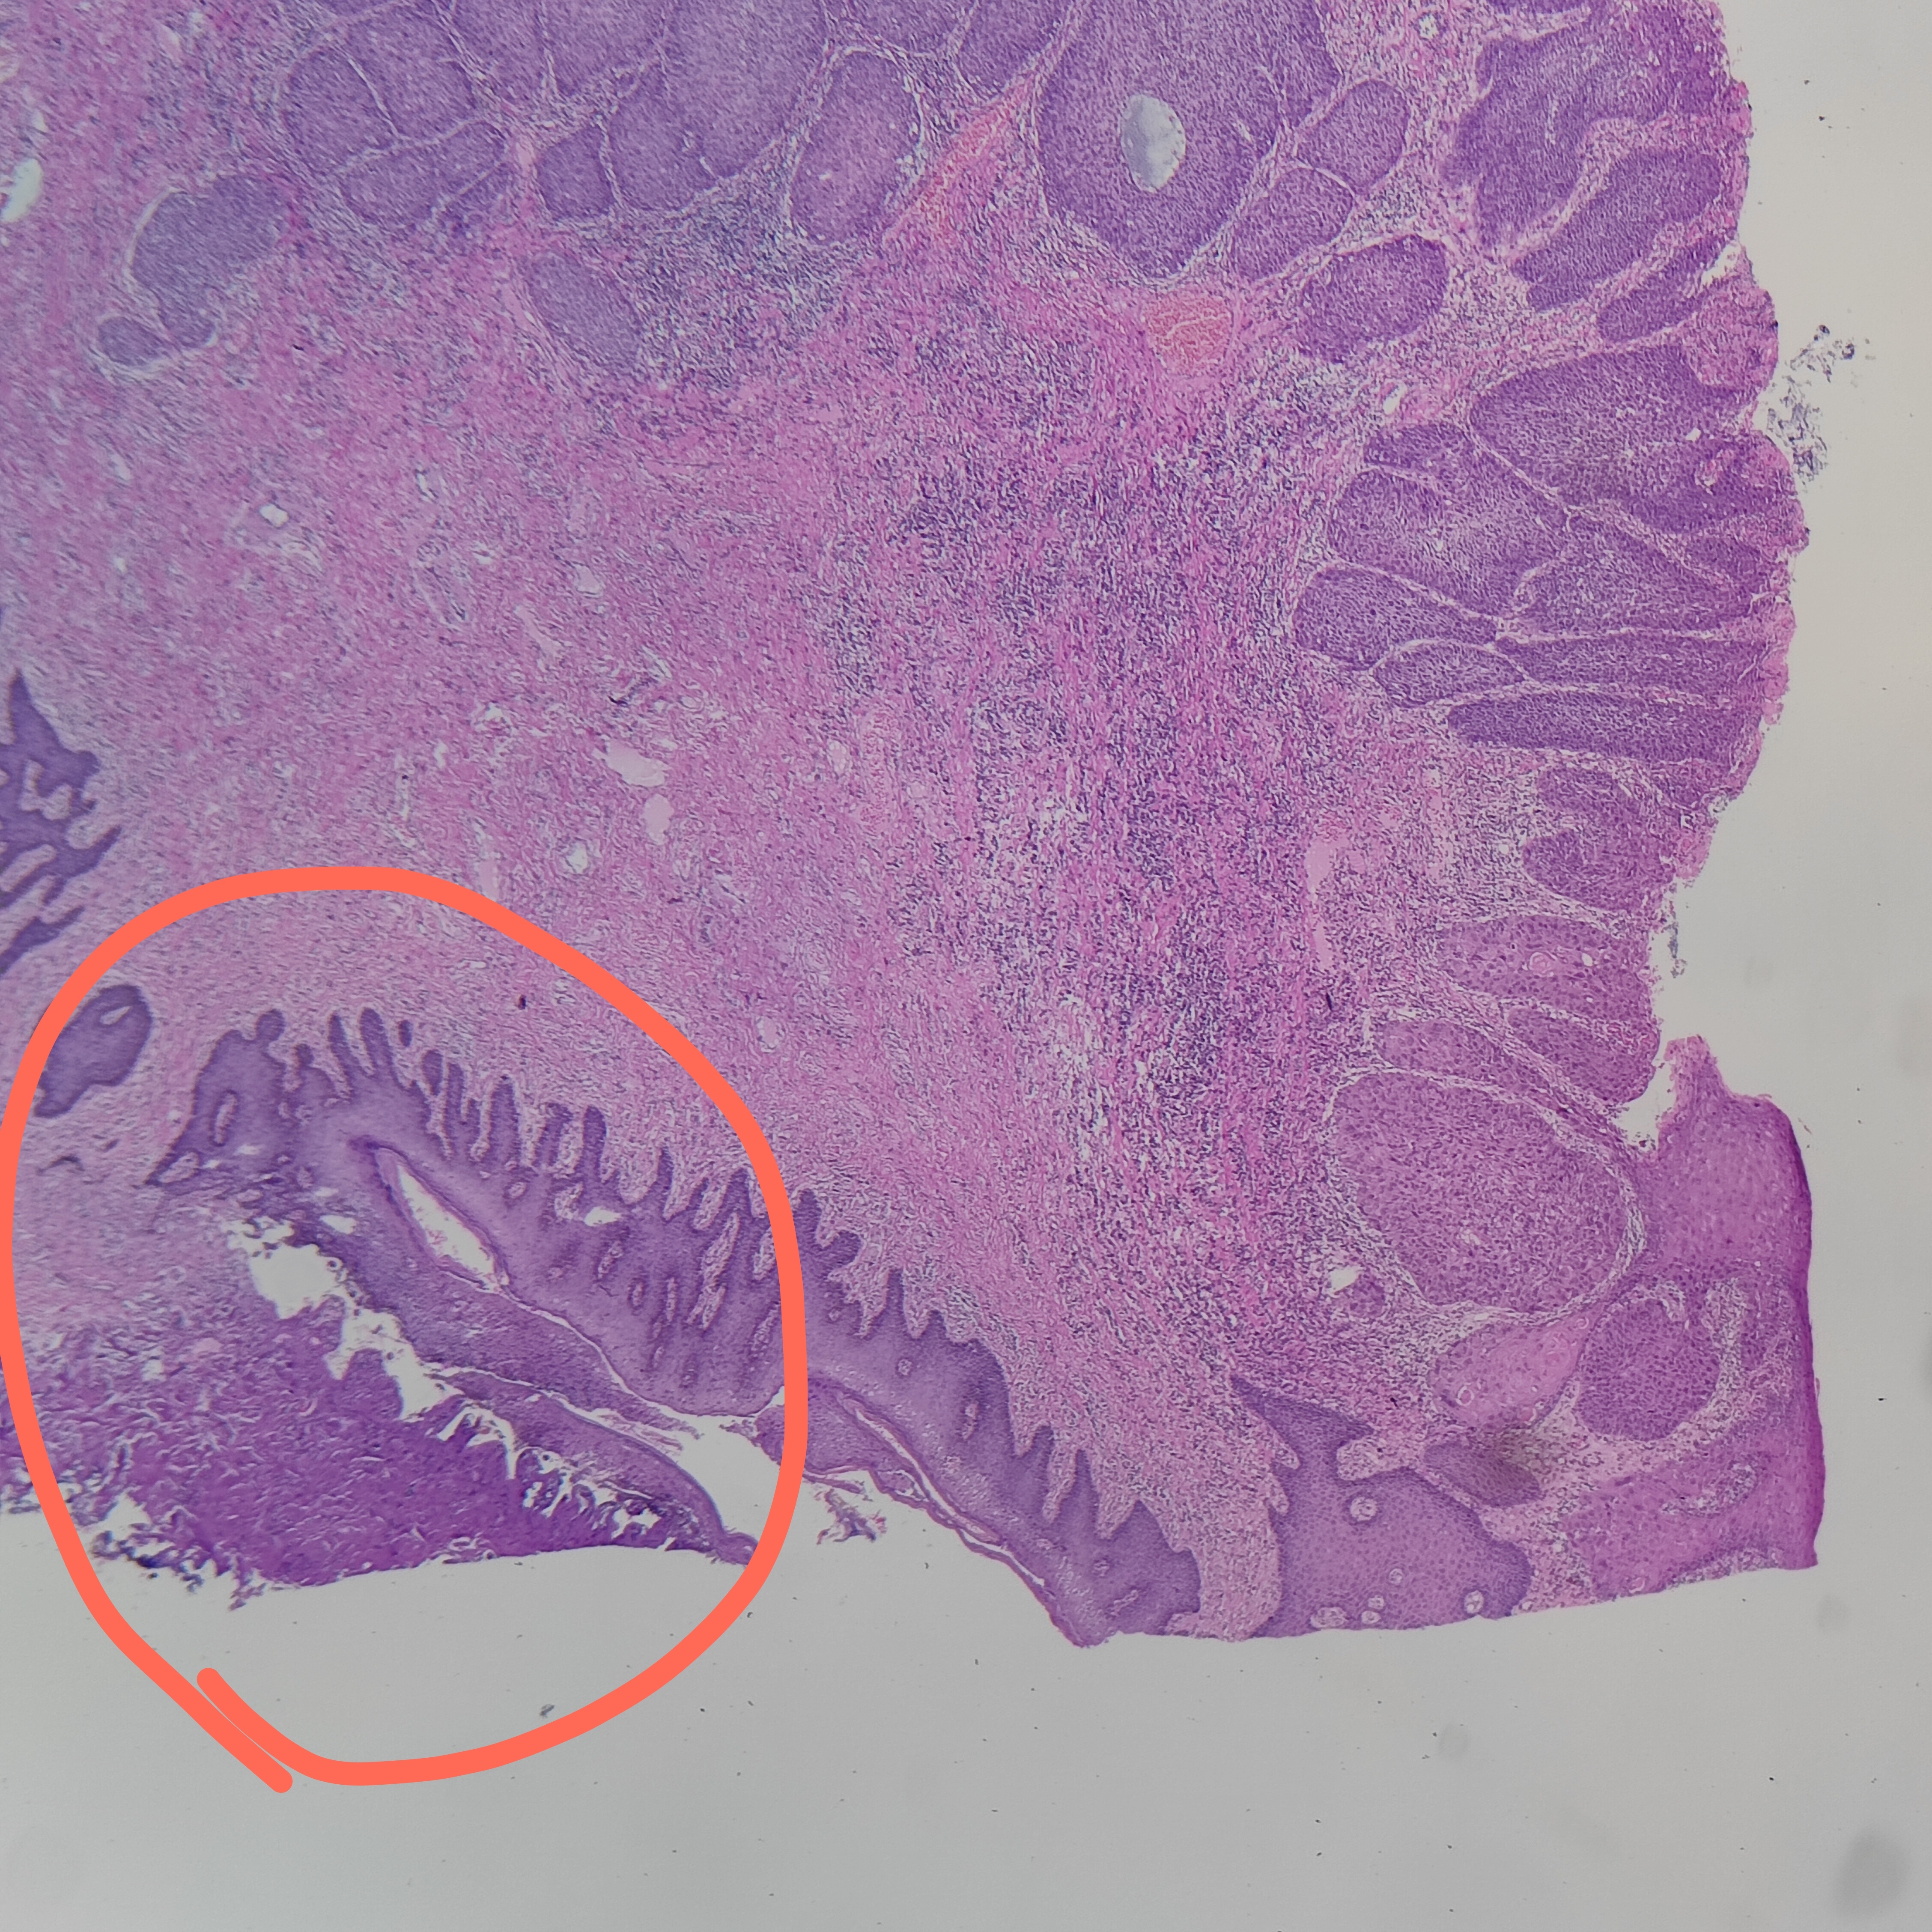

最近會診一例肛管息肉切除后的病例,原單位報了鱗狀細胞癌,但是沒報切緣情況,可能口頭告訴了手術(shù)醫(yī)生切緣不干凈,與臨床手術(shù)切除的實際情況不符合。簡單問了家屬會診的原因,手術(shù)醫(yī)生就是要看切緣是不是真正累及??戳饲衅院螅谝桓杏X就是在切片中這個部位沒看到切緣,切得很平整,應(yīng)該不是切緣。兩種情況:一是病理取材時沒取切緣,一是真正切緣還在蠟塊里面,沒有切出來。家屬反應(yīng)手術(shù)醫(yī)生說已經(jīng)切干凈了,我問那有沒有大體的照片,家屬拿出手術(shù)后的照片從上面這張圖可以看出,腫塊是一個寬蒂的息肉,手術(shù)時是有切緣的。后面就讓家屬回原單位首先確認(rèn)是否全取材,有沒有包括切緣,可以把上面這種大體照片拿出來給他們看。第二如果全部取材了,最好深切蠟塊顯露真正切緣。家屬到原單位后,解釋不清,隨即打電話給我,我把情況跟對方同行解釋了一下,回復(fù)已經(jīng)全部取材,切緣就在切片里面,臨床醫(yī)生就是沒有切干凈,后面一定要擴大切除。沒辦法,只好讓對方把蠟塊給家屬帶上,我們對蠟塊進行了深切。深切之后的切片就看得很清楚了,畫圈部分就是切緣,而且有電灼傷的痕跡,說明切緣是干凈的。經(jīng)過我們的深入工作,病人就避免了二次手術(shù)。所以,病理醫(yī)生對這樣的標(biāo)本一定要關(guān)注切緣的取材,看切片時不能忽略切緣,要知道什么時候應(yīng)該回看蠟塊,回看標(biāo)本,什么時候要深切蠟塊,不能怕麻煩。對于臨床有疑問的一定要認(rèn)真面對,仔細查找漏洞,如果有問題就實話實說。沒有問題也要實話實說。